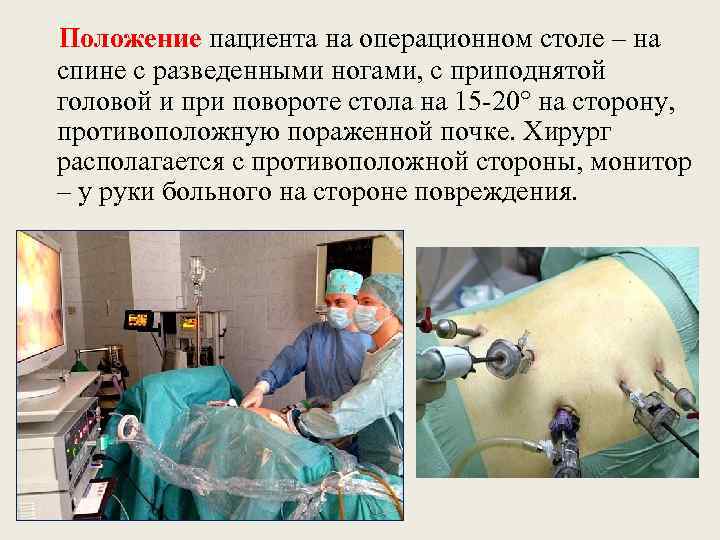

Положение пациента на операционном столе – на спине с разведенными ногами, с приподнятой головой и при повороте стола на 15 -20° на сторону, противоположную пораженной почке. Хирург располагается с противоположной стороны, монитор – у руки больного на стороне повреждения.